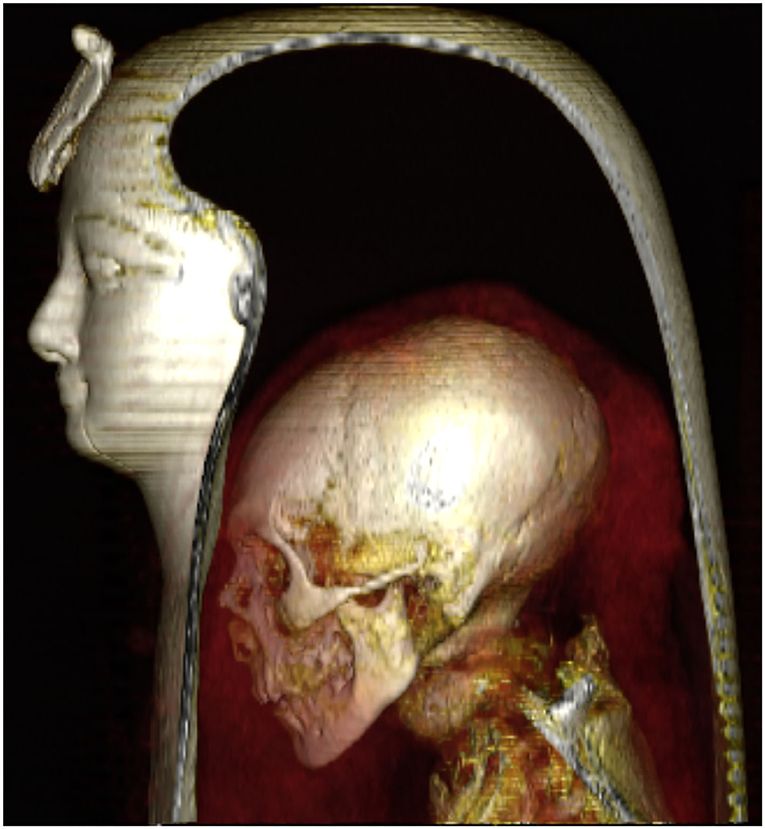

Por 140 anos, os cientistas não quiseram desembrulhar o corpo do rei com medo de danificar sua ornamentada máscara facial e bandagens.

Mas, graças à tecnologia de tomografia computadorizada (TC), os pesquisadores da Universidade do Cairo recentemente “desembrulharam” Amenhotep digitalmente para aprender sobre sua vida e dinastia.

Esse dano foi “reparado com amor” pelos padres mortuários da 21ª Dinastia, cerca de 400 anos após a morte de Amenhotep. Eles usaram uma faixa de linho tratada com resina para recolocar a cabeça e o pescoço juntos.